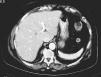

Cáncer de mama: evolución de una paciente durante 17 años